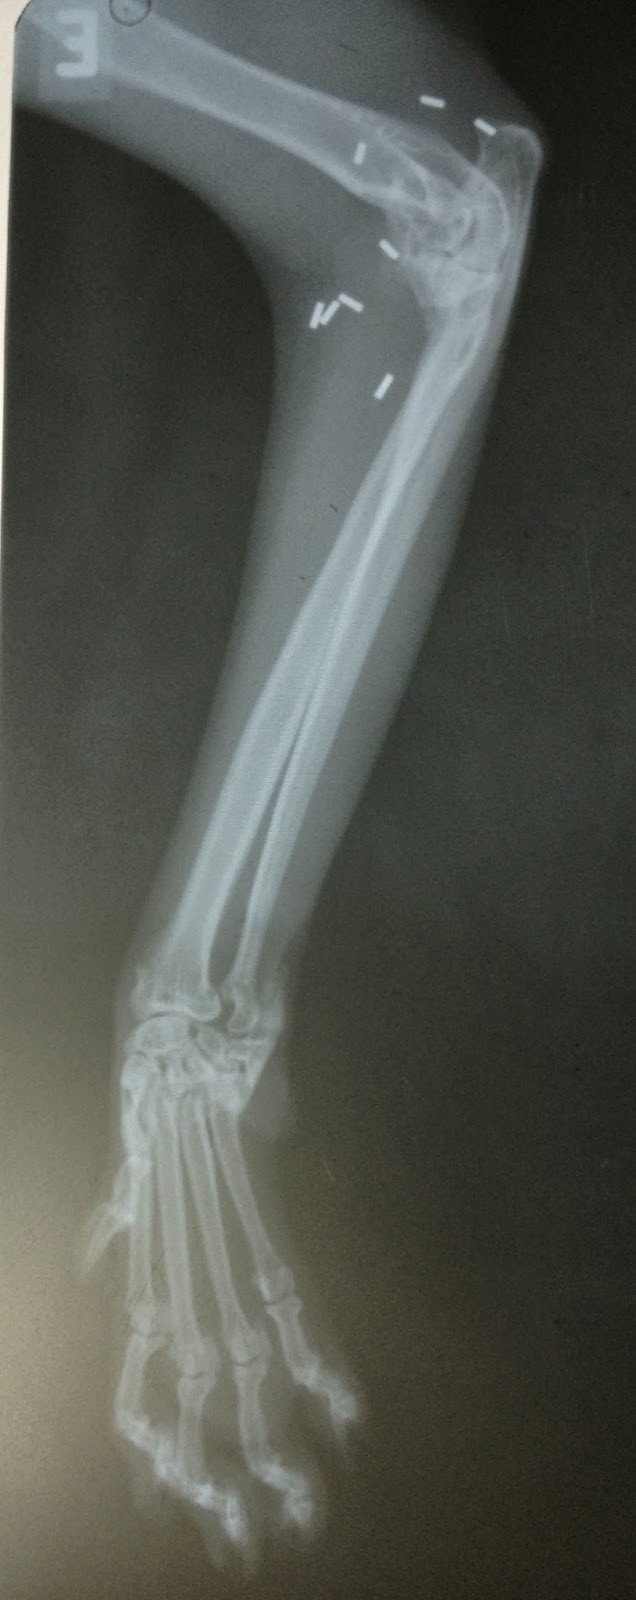

Naquela época ela ficou bem, e para minha surpresa a She-Ra e sua dona me procuraram este ano novamente com a queixa de que estava mancando novamente com a pata da frente. Quando foram ao veterinário tirar outra radiografia, descobriram que ela estava com artrose na outra pata (direita), e uma surpresa muito legal: a radiografia da pata esquerda mostrava que a artrose onde foi feito o implante de ouro há 2 anos tinha diminuído! E até na palpação pareceu que estava com menos volume no local. Ah, e ela deixou apertar, ou seja, está sem dor!

Como já tínhamos um histórico de sucesso com a pata esquerda, não pensamos duas vezes: na semana seguinte fizemos o implante de ouro na pata direita, pois estava doendo muito, ela não podia nem enocostar a patinha no chão.